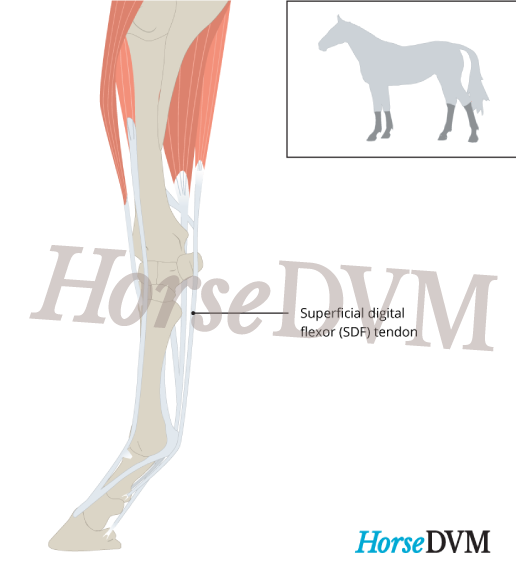

Superficial Digital Flexor (SDF) Tendinitis | HorseDVM Diseases A-Z

Superficial Digital Flexor (SDF) Tendinitis | HorseDVM Diseases A-Z